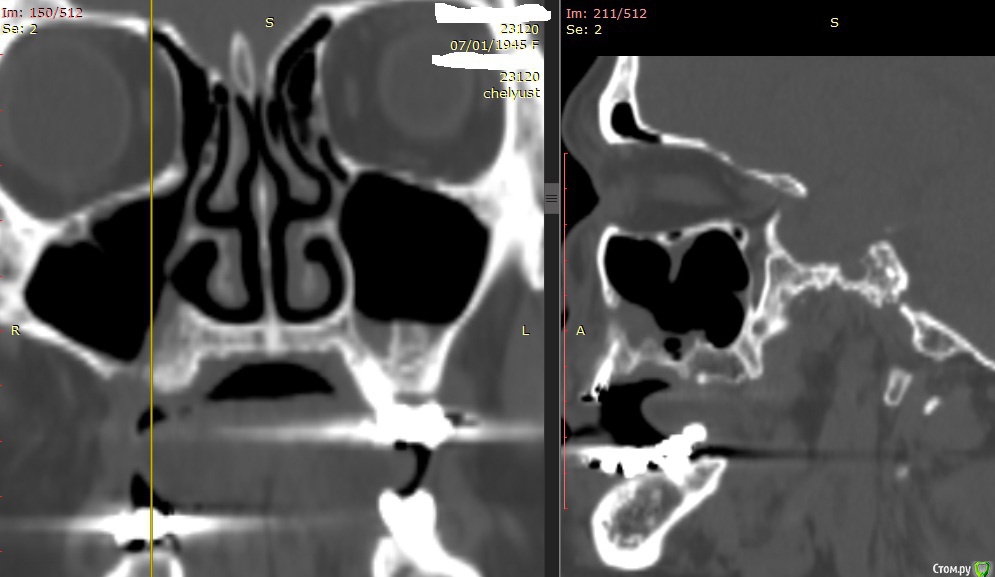

Alexey Doc Опубликовано 29 апреля, 2015 Поделиться Опубликовано 29 апреля, 2015 В клинику с целью протезирования обратилась пациентка 70 лет.Ортопед направил на консультацию. В анамнезе: со слов больной год назад удален зуб 1.6 после чего сформировался оро-антральный свищ. В январе 2015 года выполнена правосторонняя радикальная гайморотомия с удалением 1.5, 1.7 зубов. Сопутствующая патология в стадии компенсации.На сегоднещний день жалоб кроме отсутствия зубов нет.В полости рта : верхний свод преддверия справа плавно перетекает в небо мощным тяжем подвижной слизистой шириной примерно 15-17 мм . Альвеолярный отросток отсутствует. Какой\ие минимально инвазивные( учитывая возраст пациентки) способы аугментации вы бы применили у этой больной для последующего протезирования с опорой на имплантатах? Буду рад любому мнению и рац.предложению.Ниже свежие срезы КТ. Ссылка на комментарий

krokomot Опубликовано 29 апреля, 2015 Поделиться Опубликовано 29 апреля, 2015 Мне кажется минимально инвазивно врядли обойдешься. подвижная слизистая всю имплантацию испортит. Если пофантазировать, то можно попробовать имплантацию в скуловую кость или поднадкостничный вариант(индивидуальный), с поднадкостничным вариантом все равно придется все располосовать + заказывать фрезеровку из титана или кхс, приживляесмость кто его знает как пойдет)), но остеоинтеграция тут и не нужна. Чем не вариант для бабули 70 лет)) Ссылка на комментарий

Bier Опубликовано 29 апреля, 2015 Поделиться Опубликовано 29 апреля, 2015 Бабуля может еще 30 проживет...Я за зигомы Ссылка на комментарий

Alexey Doc Опубликовано 30 апреля, 2015 Автор Поделиться Опубликовано 30 апреля, 2015 Бабуля может еще 30 проживет...Я за зигомыЗигомами не владею.Вот еще пара картинок реконструкции Ссылка на комментарий